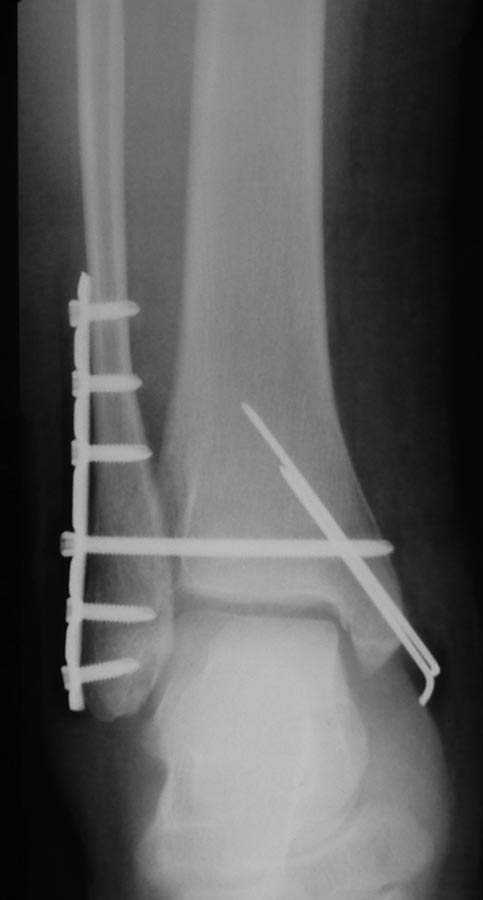

Немедленно удалить "позиционный" винт, который работает как болт-стяжка и синдесмоз явно перетянут. Учитывая форму тарана, иной установки стопы ожидать сложно, оптимально спицы заменить на винт.

Отправлял до- и послеоперационные снимки, но почему-то проявились только послеоперационные. Досылаю остальные.

как можно перетянуть таким винтом синдесмоз,ладно обычным кортикальным,а этим....+винт вообще недотянут,головка винта выпирает.подтянутые вровень,а этот выпирает.не?

С винтом тут понятно. Пластина блокируемая. Винты ввинчены в нее заподлицо. А синдесмозный введен под углом. Это синтезовская пластина. Угол введения только один, прямой. Поэтому головка синдесмозного винта и не могла погрузиться полностью. Но синдесмоз не перетянут, это правда.

Я поддержу Максима. Не нравиться мне остеосинтез! Имплант модный, современный, репозиция наружной лодыжки идеальная, суставная щель какаду-то равномерная.....Какбуд-то.

Про репозицию: Медиальная лодыжка чуть не дорепонированв, реально медиальное щель уже, чем в норме. Про синдсмоз по этим проекциям судить нельзя. Сделайте КТ - можете удивиться тому, что найдете.

Про остеосинтез: перелом наружной лодыжки простой, отремонтирован идеально, а где стягивающий винт? Межберцовый винт: в его качестве locking had screw, а не обычный кортикальный? В каких руководствах или статьях есть такая рекомендация? Этот винт проведен через сам синдесмоз на 1 см проксимальнее сустава - а это в соответствии с какими рекомендациями? Вроде рекомендуют повыше немного?

Перед введением позиционного винта берцовые кости сжал пальцами одной руки. Спокойно, без мата. Через противоположный кортикал винт провел из-за того, что после остесинтеза наружной лодыжки щель синдесмоза все-таки оставалась расширенной и легко сжималась пальцами руки. Теоретически это может происходить из-за неточной репозиции наружной лодыжки. Но, насколько я видел во время операции - репозиция была точной. И еще раз повторю, что после проведения винта через противоположный кортикал, вывинтил его обратно на 2-3 оборота, ориентируясь под ЭОПом на здоровую конечность.